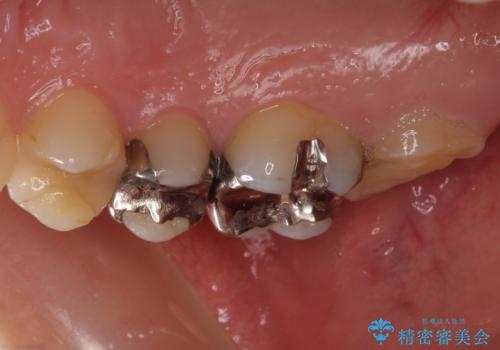

- 右上下の奥歯がむし歯でしみたり痛んだりするとのことで来院された患者様です。

下顎の奥歯は強い痛みを感じており、既に歯髄に不可逆的な炎症が起きていると診断されたため、根管治療の後にセラミッククラウンにて補綴治療を行うこととしました。

上顎の奥歯は最近銀歯による治療を行ったとのことでしたが、適合が不十分であり隙間からしみていたため、適合の良いゴールドインレーにて修復治療を行うこととしました。

下顎のむし歯は歯肉の中にまで及んでいたため、一部歯槽骨を削除し、歯肉縁上に健全歯質が位置するよう外科処置を併用しました。